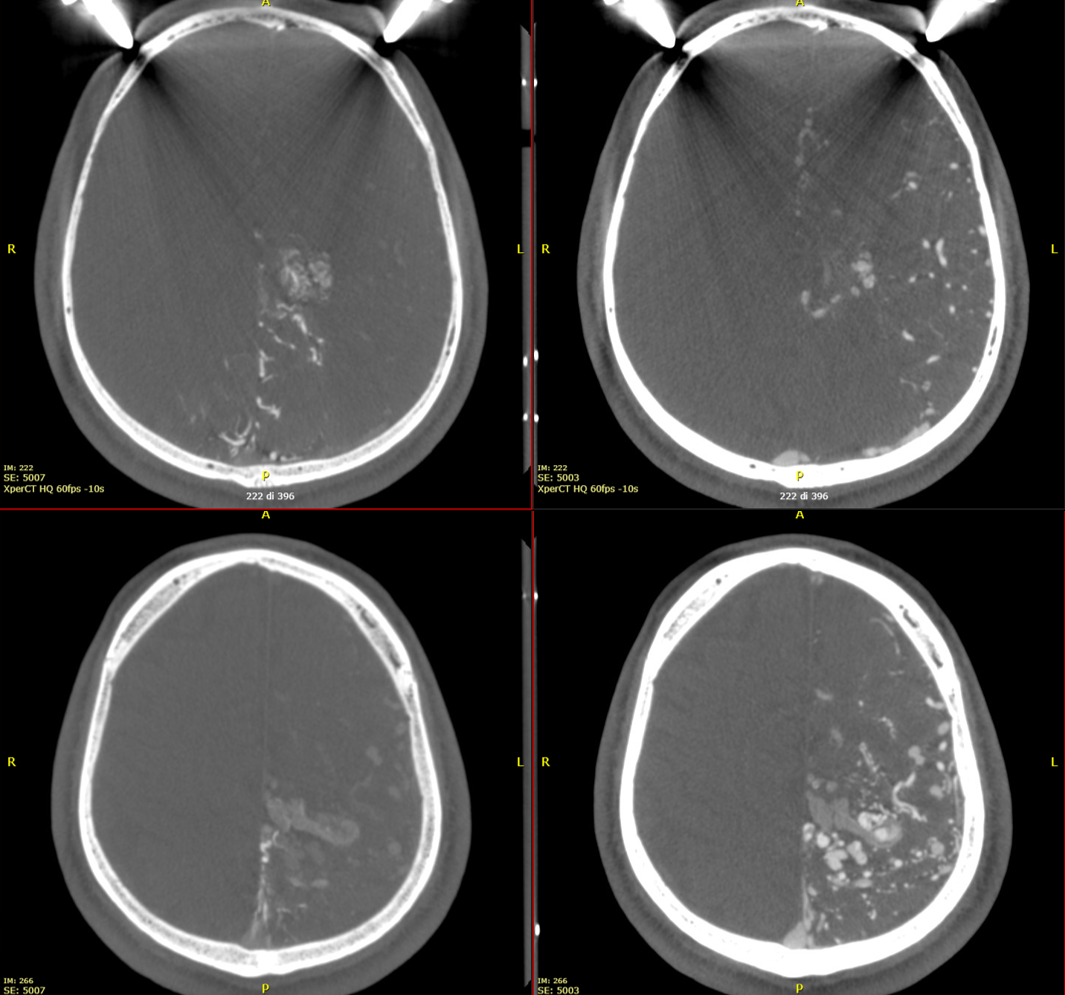

This is an Xper-CT acquisition done with the 48 cm FOV, HR 60 fps, 10-seconds protocol. We manually injected 30 ml of 50% contrast media (250 mg/ml), with a 30 ml syringe, beginning the injection 4-5 seconds before starting the acquisition.

The first pass to have good Xper-CT images for GammaKnife is a new reconstruction with 100% FOV, stent protocol, and 5123 resolution. The reconstruction must include the whole head.

Images will be sharper and with better contrast resolution.

Right and left ICA injections

Vert Injection